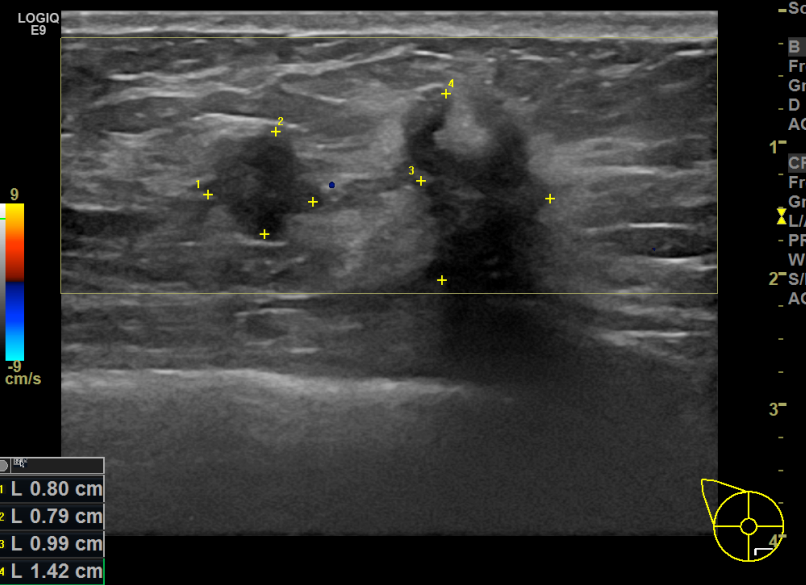

아산유외과개원후 725번째 유방암진단

상기환자 외부건진상 이상소견으로 조직검사권유받고 내원하신 40대 여성분으로 우측에다발로유방멍울 조직검사시행후 유방암 진단되었습니다.